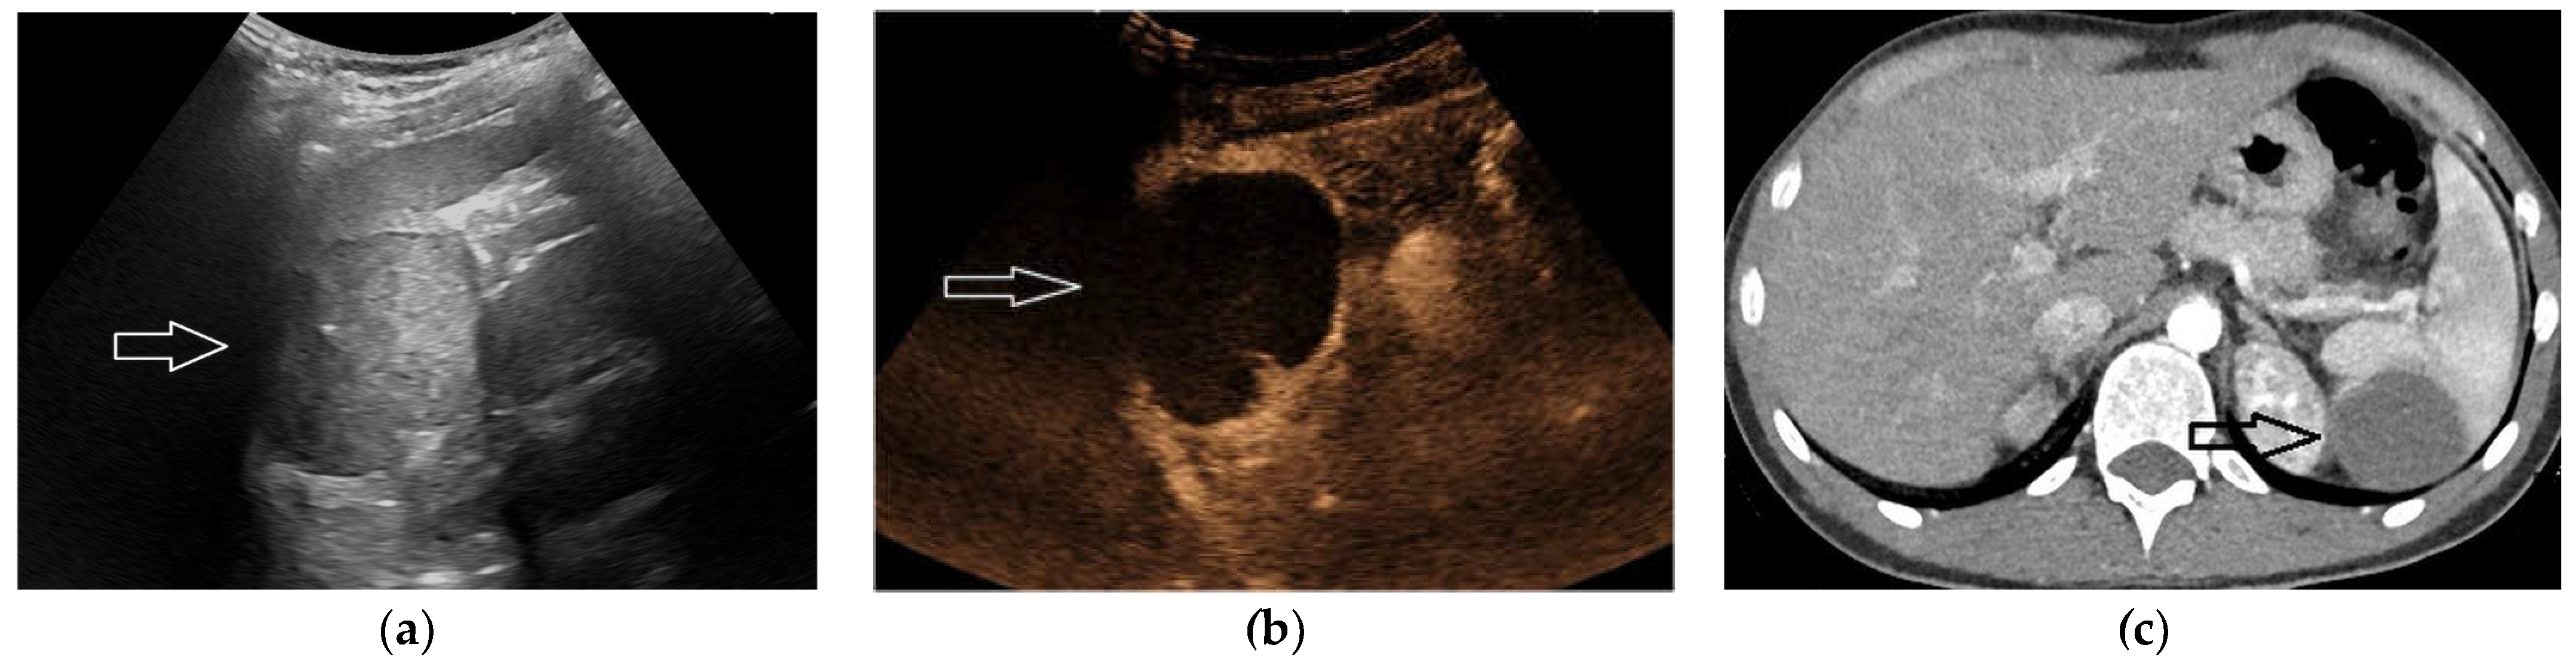

2.4. Cystic Lesions

2.5. Hematoma and Abscess